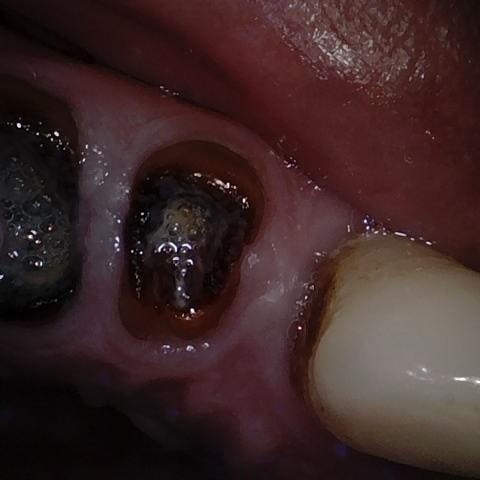

Annotated as "Good"